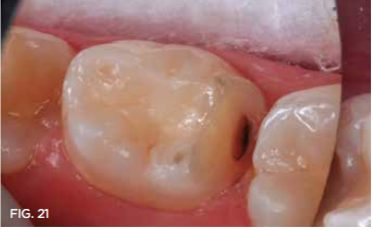

Case 5. A bite wing radiograph (not shown) revealed a distal caries lesion on a mandibular molar in a 10-year-old girl. The girl's father was informed of the need for treatment to avoid caries spread to the mesial surface of the permanent first molar. He readily agreed to SDF application rather than Class II restoration, so that his daughter could avoid a local anesthetic injection and he could save the expense. With cotton roll isolation and no local anesthetic injection, the distal caries lesion was exposed using a high-speed diamond bur (Figure 18 and Figure 19). Only one application of SDF was used in this case, followed by application of fluoride varnish (Figure 20 and Figure 21). In 7 months, the primary second molar had exfoliated, and only a trace of SDF stain remained on the permanent molar (Figure 22).

Fig 21. A few minutes after SDF application.

Fig 21